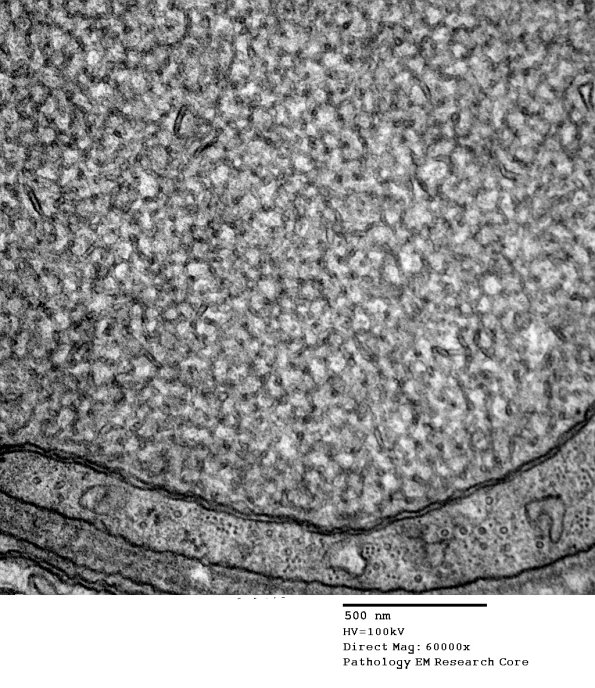

Higher magnification of image #11K1. (electron micrograph)